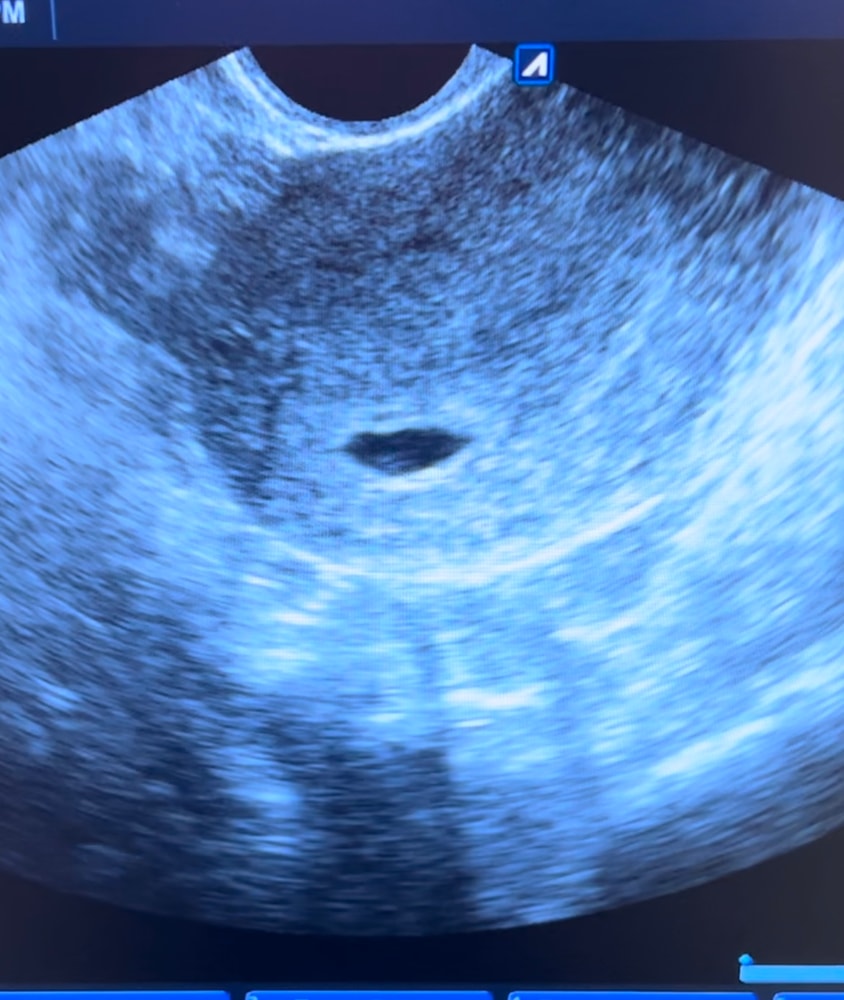

Алёна Хаустова, на узи мне утверждали что там нет эмбриона, но смотря на записи у меня какие то сомнения, как будто я тоже вижу что он есть

Я отчётливо вижу круглый ЖМ и к нему присоединен совсем еще крошечный эмбриончик.

Виктория Рыгина, странная врач 😅Пульсация это значит сердечко бьётся , просто еще не уловить чсс и не прослушать. А какое сердце может быть в ЖМ , ну п&здец конечно 🤦♀️Переделайте узи в другом месте, на фото ПЯ не пустое точно.

Сделайте в другой клинике,если сомневаетесь, хотя всё очевидно на мой взгляд)

У вас там колечко с бриллиантом)) просто плохое качество